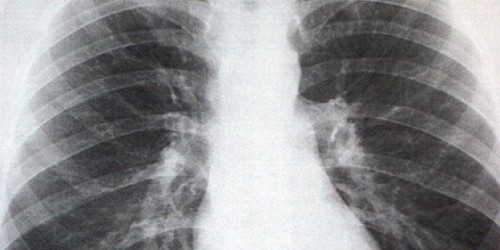

You can break your sternum, the bone in the middle of the chest, but it is VERY tough.  You can also fracture a rib.  It could also be a sprain, there are lots of muscles in your chest.